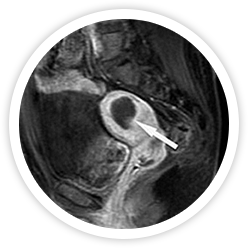

• 시술 직후 시술 직후

하이푸 시술 직후 MRI 조영증강영상에 뚜렷하게 혈류가 차단된 비관류 구역을 보임